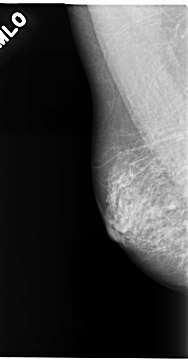

C_0141_1.LEFT_MLO

LEFT_MLO LINES 4672 PIXELS_PER_LINE 2584 BITS_PER_PIXEL 12 RESOLUTION 50 OVERLAY